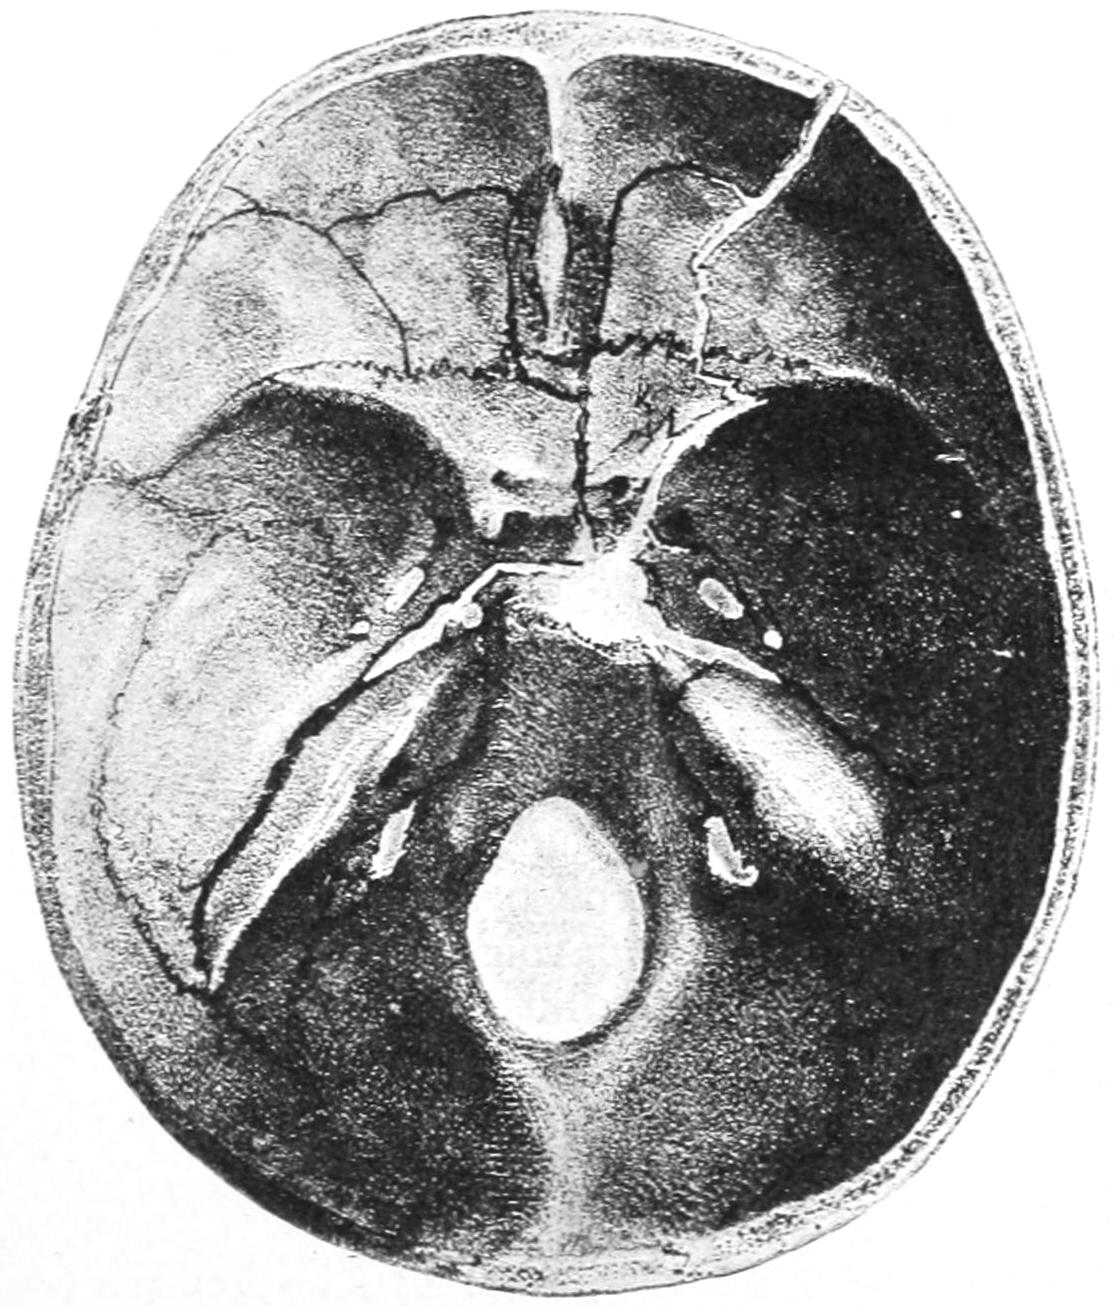

PLATE I

Fig. I.

Fig. II.

Fig. III.

Fig. IV.

Fig. V.

Fig. VI.

Fig. VII.

Fig. VIII.

DRAWN BY J. N. Z. CHASE

PLATE I.

BLOOD.

(Ehrlich triple stain.)

(Prepared by Dr. I. P. Lyon.)

Fig. I. TYPES OF LEUCOCYTES.

a. Polymorphonuclear Neutrophile. b. Polymorphonuclear Eosinophile. c. Myelocyte (Neutrophilic). d. Eosinophilic Myelocyte. e. Large Lymphocyte (large Mononuclear). f. Small Lymphocyte (small Mononuclear).

Fig. II. NORMAL BLOOD.

Field contains one neutrophile. Reds are normal.

Fig. III. ANÆMIA, POST-OPERATIVE (secondary).

The reds are fewer than normal, and are deficient in hæmoglobin and somewhat irregular in form. One normoblast is seen in the field, and two neutrophiles and one small lymphocyte, showing a marked post-hæmorrhagic anæmia, with leucocytosis.

Fig. IV. LEUCOCYTOSIS, INFLAMMATORY.

The reds are normal. A marked leucocytosis is shown, with five neutrophiles and one small lymphocyte. This illustration may also serve the purpose of showing the leucocytosis of malignant tumor.

Fig. V. TRICHINOSIS.

A marked leucocytosis is shown, consisting of an eosinophilia.

Fig. VI. LYMPHATIC LEUKÆMIA.

Slight anæmia. A large relative and absolute increase of the lymphocytes (chiefly the small lymphocytes) is shown.

Fig. VII. SPLENO-MYELOGENOUS LEUKÆMIA.

The reds show a secondary anæmia. Two normoblasts are shown. The leucocytosis is massive. Twenty leucocytes are shown, consisting of nine neutrophiles, seven myelocytes, two small lymphocytes, one eosinophile (polymorphonuclear) and one eosinophilic myelocyte. Note the polymorphous condition of the leucocytes, i. e., their variations from the typical in size and form.

Fig. VIII. VARIETIES OF RED CORPUSCLES.

a. Normal Red Corpuscle (normocyte). b, c. Anæmic Red Corpuscles. d-g. Poikilocytes. h. Microcyte. i. Megalocyte. j-n. Nucleated Red Corpuscles. j, k. Normoblasts. l. Microblast. m, n. Megaloblasts.

The value of a careful blood examination is well illustrated by Plate I, prepared by Dr. Irving P. Lyon, in which are displayed the alterations of greatest interest to the surgeon.